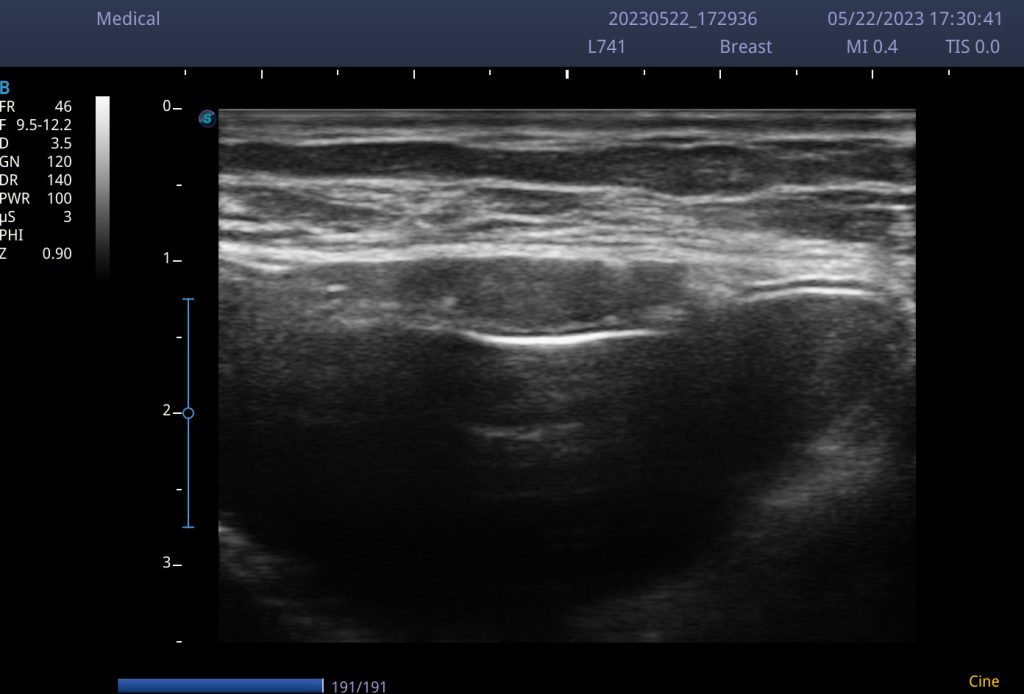

Po povečanju prsi s silikonskimi vsadki poleg rednega samopregledovanja svetujemo tudi redne kontrole pri izbranem kirurgu ter sledenje vsadkov z obdobnimi slikovnimi preiskavami kot sta ultrazvočni pregled (UZ) ali pa magnetno resonančno slikanje (MR). Ultrazvočni pregled prsnih vsadkov je v primerjavi z MR slikanjem hitrejša in lažje dostopna preiskava s katero lahko spremljamo stanje vsadkov in zaznamo njihovo morebitno poškodbo. Po povečanju prsi priporočamo prvi UZ pregled vsadkov 5 let po operativnem posegu ter nato na 2-3 leti. UZ vsadkov je smiselno opraviti tudi ob sumu na njihovo poškodbo, ob npr. hudih udarcih v prsni koš, po prometnih nezgodah ali športnih poškodbah prsnega koša (padci). Sodobni prsni vsadki priznanih svetovnih proizvajalcev lahko ostanejo v telesu doživljenjsko in jih, v kolikor ostanejo nepoškodovani, ni potrebno zamenjati, zato je njihovo redno spremljanje z UZ ali MR preiskavo ključnega pomena. Na kliniki Medved estetika svojim strankam omogočamo redne UZ kontrole vsadkov, obenem pa UZ pregled nudimo tudi tistim, ki so poseg povečanja prsi izvedle drugje.

Ultrazvočni pregled prsnih vsadkov je hitra in povsem neboleča preiskava s katero spremljamo stanje vsadkov. Z njim lahko zaznamo spremembe v sestavi, obliki in položaju vsadka ter na ta način ocenimo njegovo intaktnost ali zaznamo morebitno poškodbo (rupturo). Prikažemo si lahko morebitno tekočino ob vsadku ter ocenimo stanje vezivne ovojnice, ki obdaja vsadek. Z UZ preiskavo lahko vsadke spremljamo od operativnega posega dalje, še posebej pa je priporočljivo spremljanje, če je od posega minilo že več kot 5 let.